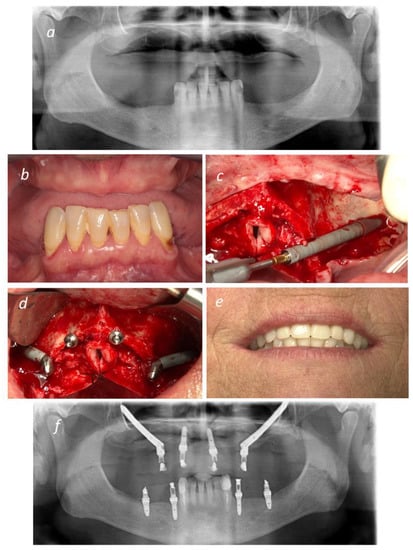

2. Materials and Methods

2.1. Surgical Protocol

2.2. Immediate and Final Prosthetic Protocol